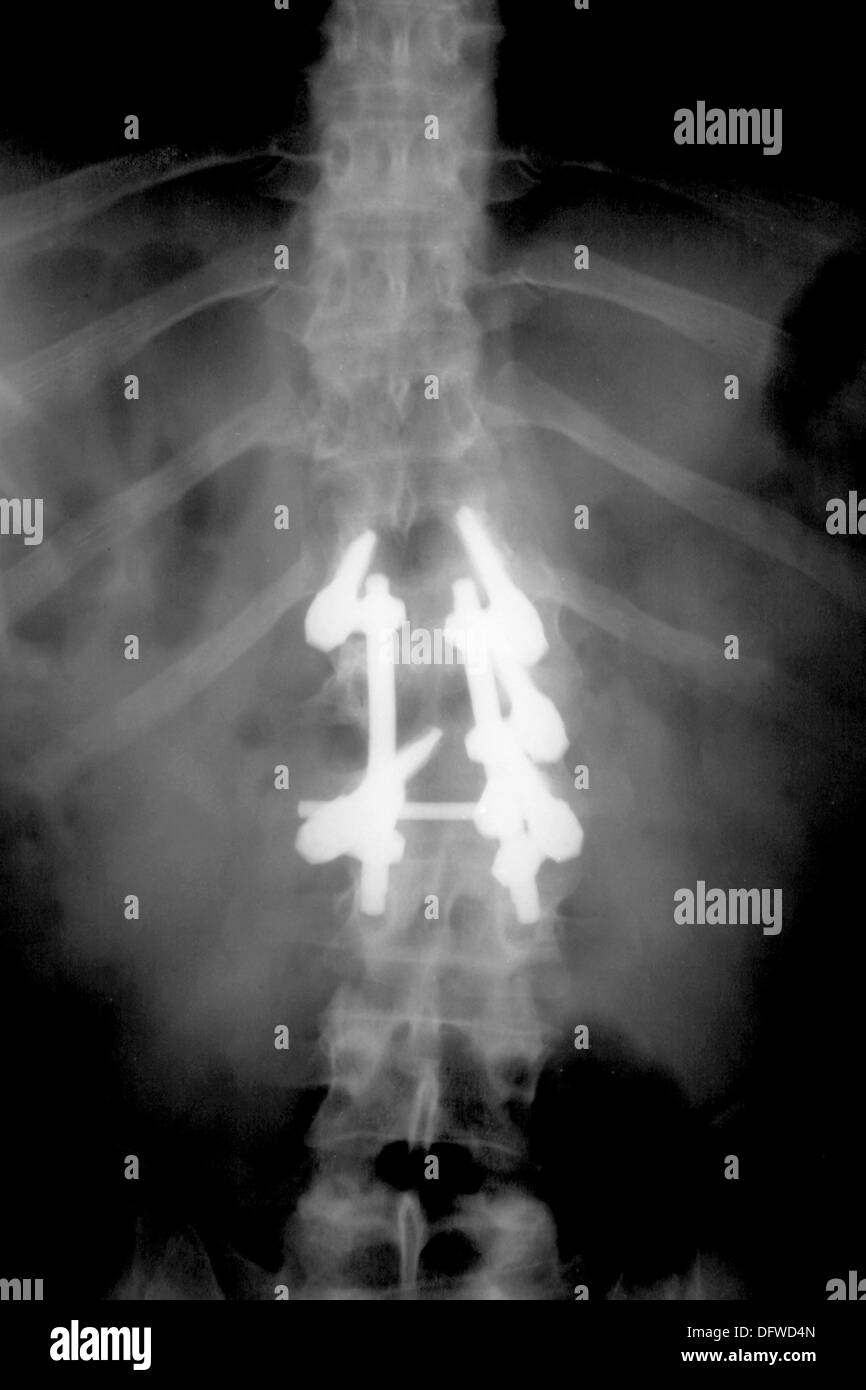

From www.alamy.com

Titanium fixations on spine, compression fractures caused by car Can A Car Accident Cause A Spinal Compression Fracture Even if you need surgery to repair your broken. Spinal fractures are usually caused by osteoporosis or traumas like car accidents. Recovering from a spinal compression fracture requires a careful balance of rest, therapy, and avoiding activities that can. This could include falls, car accidents or other types of physical trauma. Car accidents are a rising trend in spine injuries.. Can A Car Accident Cause A Spinal Compression Fracture.

Titanium fixations on spine, compression fractures caused by car Can A Car Accident Cause A Spinal Compression Fracture Compression fractures can also be caused by trauma, such as a car accident or fall. Car accidents are a rising trend in spine injuries. Even if you need surgery to repair your broken. In such cases, the force exerted on. Spinal fractures are usually caused by osteoporosis or traumas like car accidents. Recovering from a spinal compression fracture requires a. Can A Car Accident Cause A Spinal Compression Fracture.

Titanium fixations on spine, compression fractures caused by car Can A Car Accident Cause A Spinal Compression Fracture In such cases, the force exerted on. This could include falls, car accidents or other types of physical trauma. These types of fractures are more common in younger individuals or those with healthy bones. Even if you need surgery to repair your broken. Acute trauma, such as a fall, car accident, or sports injury, can lead to spinal compression fractures.. Can A Car Accident Cause A Spinal Compression Fracture.